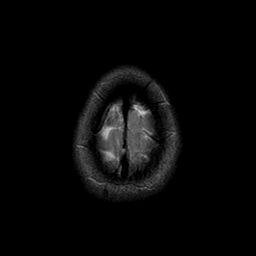

Sarcoma, MR Study #1 mr-t2 -- Slice #23

[Home][Help][Clinical] Slice 23